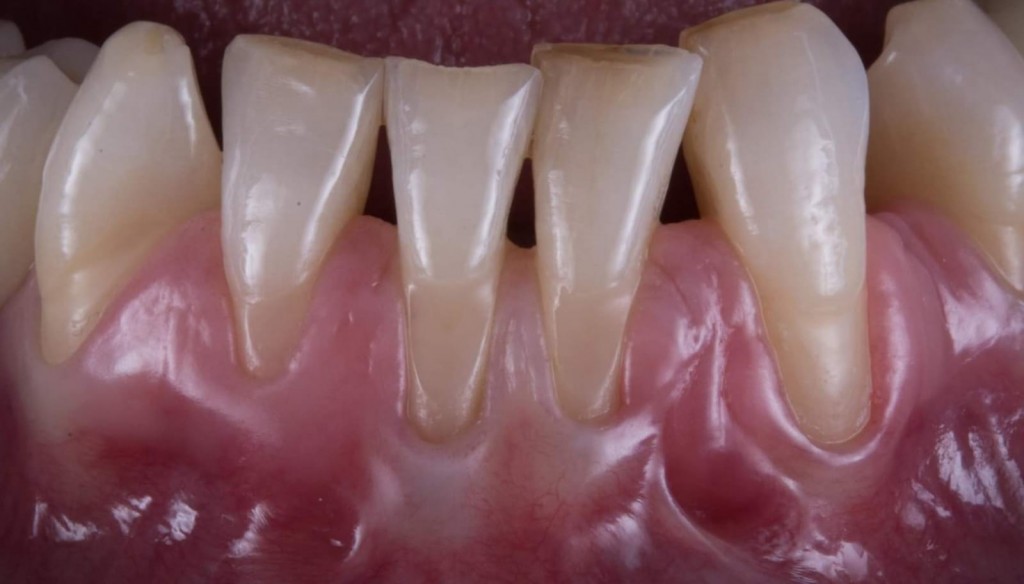

Il caso era questo.

WhatsApp Image 2019-03-13 at 18.15.02